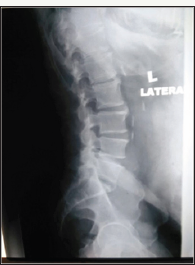

Figure 3: Preoperative and postoperative plain radiographs of a 64 years old gentleman presented with low back pain and left buttock pain. DIAM was inserted at L4/L5 level.

Figure 4: Preoperative and postoperative plain radiographs of a 64 years old gentleman presented with low back pain and left buttock pain. DIAM was inserted at L4/L5 level.